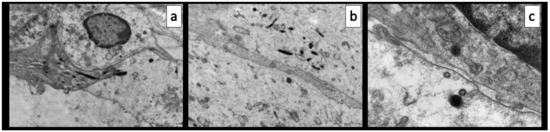

Light microscopy examination of semithin sections confirmed the lympho-monocytic inflammatory infiltrate involving the vasa vasorum in the adventitia (Figure 1d). TEM analysis of these same areas showed endothelialitis with features of endothelial cell activation, e.g., enlarged, euchromatinic nuclei; hypertrophy of Golgi complexes; increased number of Weibel–Palade bodies; and injury, e.g., ballooning with clear cytoplasm and junctional leakage (Figure 3). The presence of Weibel–Palade bodies together with the immunoreactivity for FVIII seems to indicate a pro-thrombotic stimulus in the arterial and capillary endothelial cells, while venular endothelial cells were negative.

Consistent with previous reports, we found increased cytoplasmatic endocytic and round virus-like particles, 120 nm in diameter, with a fuzzy, proteinaceous crown (Figure 3).

Figure 3. Transmission electron microscopy of the case report. (a) Endothelialitis, clear cytoplasm, hypertrophy of Golgi complex and abundance of Weibel–Palade bodies. (b) Junctional leakage. (c) Virus-like particles with fuzzy proteinaceous cores.